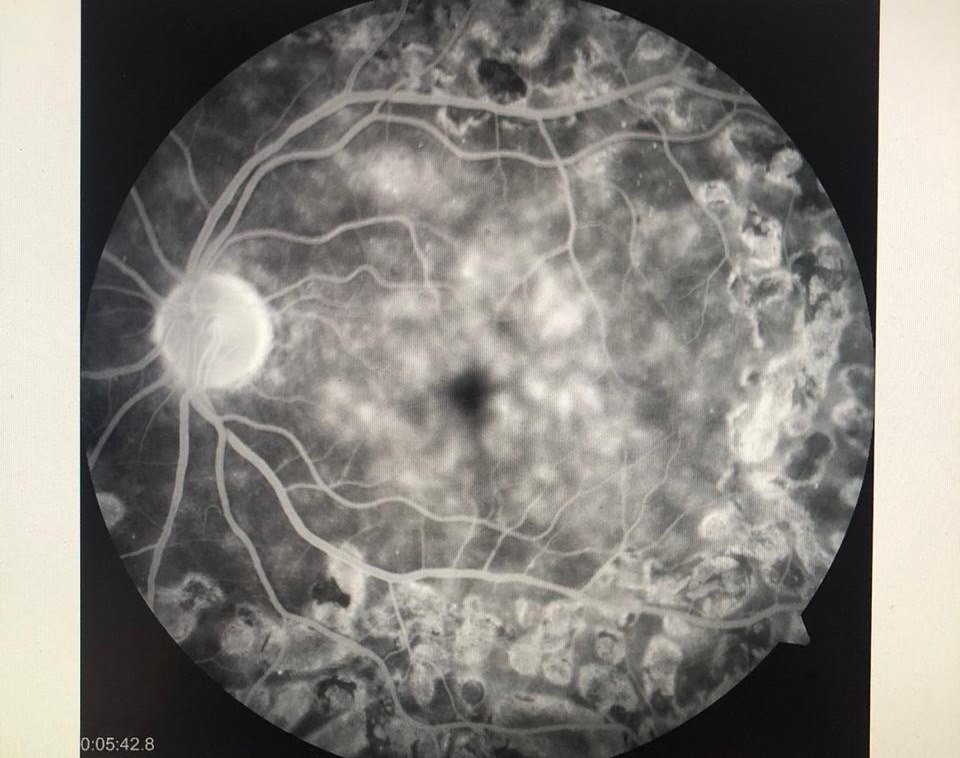

Retina

Láser, Vitrectomía, Crioterapia, Retinopexia, inyección de Antiangiogénicos y Cerclaje Escleral.

Alta especialidad en Retina, Vítreo y Oncología Ocular.

Alta especialidad en Retina y Vítreo.